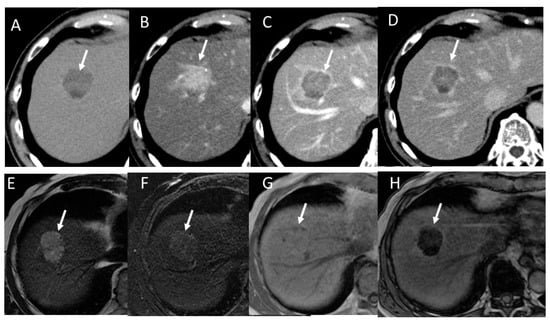

4.2. Early Hepatocellular Carcinoma (Early-HCC)

4.3. Well-Differentiated Hepatocellular Carcinoma (Well-HCC)